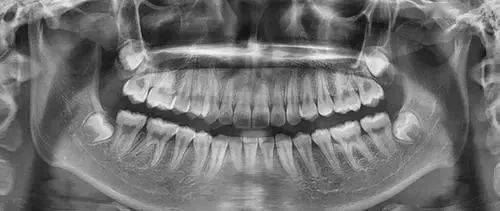

5、为什么根管治疗需要拍多张牙片?

根管治疗时,拍牙片是很有必要的,并且至少要保证3张牙片。

第一张在治疗前,帮助医生了解牙根的基本情况,制定治疗计划;

第二张在治疗中,帮助医生了解治疗情况,如根管预备是否到位等,并制定下一步治疗方案;

第三张是在治疗结束后,帮助判定根管充填质量,发现问题及时补救。